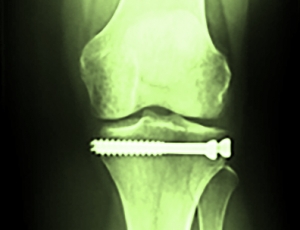

Röntgendiagnostik

Zur präzisen Diagnostik von Verletzungen und Erkrankungen am Skelett ist die Röntgendiagnostik auch heute noch unverzichtbar.

Wir verfügen über eine hochmoderne digitale Röntgenanlage und speziell geschulte Mitarbeiterinnen, die die Röntgenuntersuchung durchführen. Direkt im Anschluss werden die Bilder vom Arzt befundet und Ihnen erklärt.